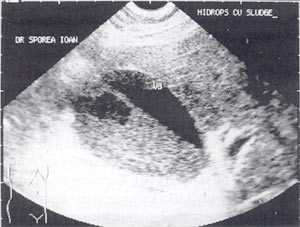

В исследовании, проведенном в США, "желчный сладж" выглядел в виде гиперэхогенного образования в желчном пузыре с горизонтальным уровнем без задней тени, форма которого медленно изменялась при движении больного [10]. Характерный признак "желчного сладжа" - изменение его вида на сканограмме в зависимости от изменения положения тела больного и медленным достижением нового горизонтального уровеня. Общим правилом является отсутствие дистальной акустической тени. Эхогенность сладжа может быть различной. Иногда сладж заполняет весь желчный пузырь, затрудняя дифференцировку между тканью печени и желчным пузырем. Эта ситуация называется "гепатизация желчного пузыря" (рис. 1).

Рис. 1. Гепатизация желчного пузыря, полностью заполненного сладжем.

Кроме типичного вида, "желчный сладж" может иметь особый вид, похожий на круглое полипоидное объемное образование с острыми краями или неравномерным контуром ("опухолеподобный желчный сладж" или "сладжевые шарики" [12, 13]). При изменении положения больного видны перекатывающиеся или разрушающиеся шарики сладжа, затем снова формирующие исходное объемное образование (рис. 2-8).

Рис. 2. Желчный пузырь, наполовину заполненный сладжем.